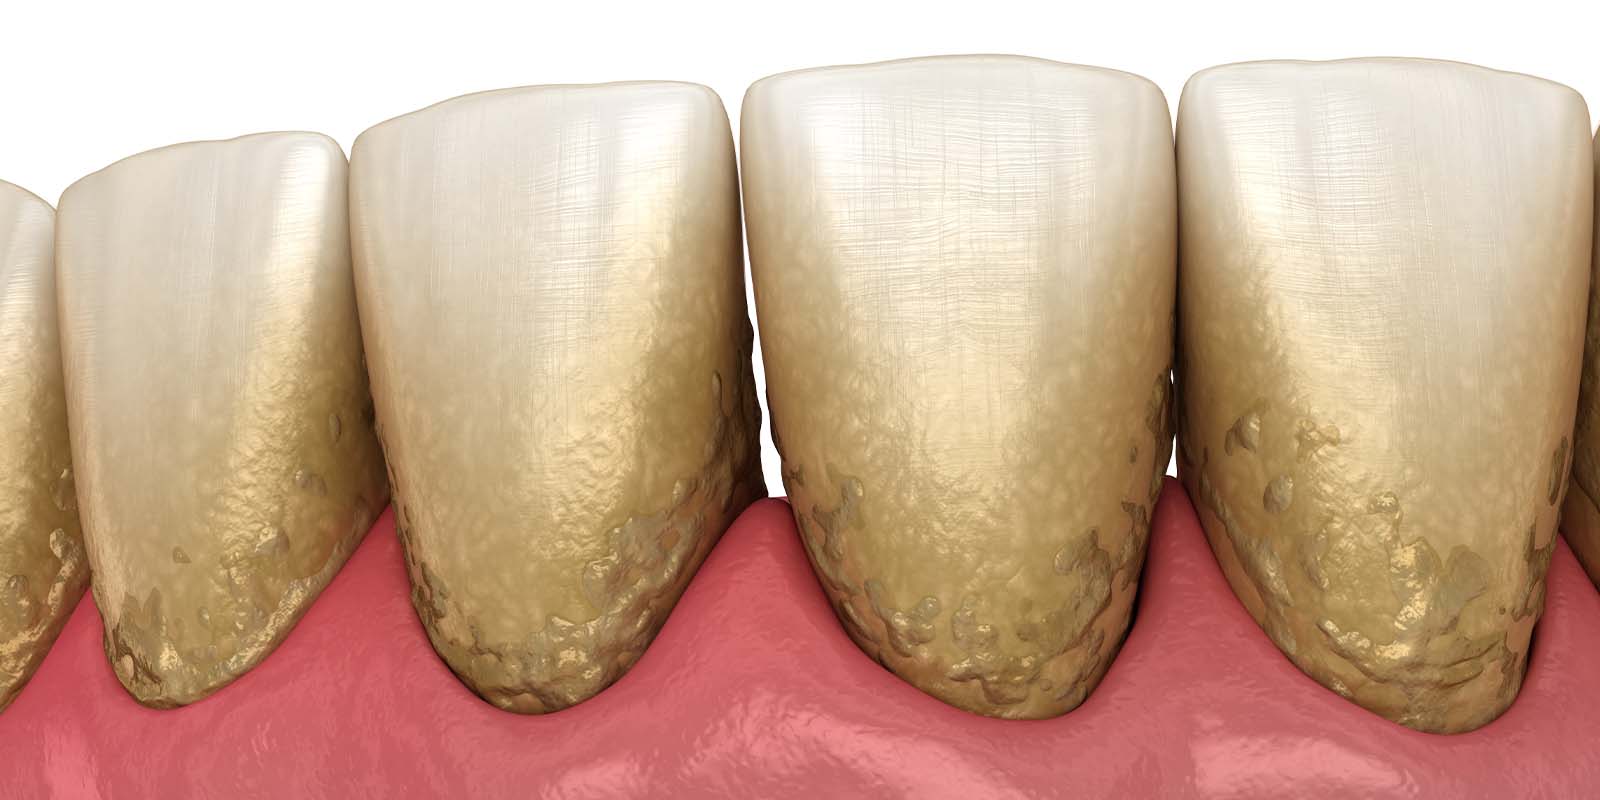

スケーリングで歯石を除去する重要性

歯石は歯垢(プラーク)が石灰化したものです。

大量の細菌が含まれていますが、歯ブラシの力では除去することができません。

特に歯周病の場合は、歯ぐきの中に歯石が入り込むため、気づかずに放置してしまう方も少なくないのです。

歯周病を悪化させないためにも、定期的なクリーニングで歯石の除去をおすすめします。